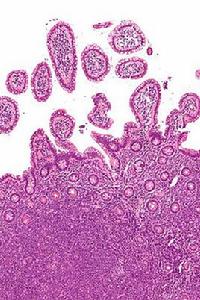

(1)組織結構:是診斷惡性淋巴瘤的基本條件之一,惡性 淋巴瘤患者早期病變,可能會傷害部分淋巴結,因此,可以保存部分或大部分淋巴結的結構以外,目前就大多數惡性淋巴瘤來說,淋巴結的結構消失是診斷惡性淋巴瘤的基本條件之一,其中包括淋巴濾泡及淋巴竇消失等等的情況。

(2)淋巴竇的消失:這是診斷惡性淋巴瘤的另一個基本條件,專家稱,這類主要表現在淋巴竇內充滿著腫瘤細胞,致竇的結構會完全消失,病變是呈瀰漫性。但是在結節性淋巴瘤,濾泡間霍奇金病,以及早期的非霍奇金淋巴瘤,淋巴竇可以完全或部分保存,特別是淋巴結的邊緣竇往往在病變後期才能受累。

(4)淋巴濾泡的消失:在結節性惡性淋巴瘤中,專家觀察說腫瘤細胞所構成的濾泡一般都是很大的,都以不一樣的大小存在著,濾泡內的腫瘤細胞均勻一致,有明顯異形性。這種類型的惡性淋巴瘤,淋巴結的基本結構好像存在,但不被認為是良性的。體弱衰竭的老年人,使用過免疫抑制劑的器官移植病人,他們的淋巴結形態學一般情況下反映免疫功能低下,缺乏淋巴濾泡的形成,不能誤認為淋巴結的結構破壞。